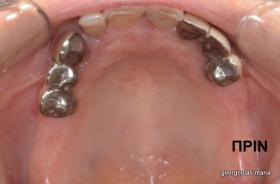

Η ασθενής αυτή είχε παλιές ακίνητες αποκαταστάσεις (γέφυρες) στην άνω γνάθο  κ μια κινητή προσθετική αποκατάσταση (μερική οδοντοστοιχία-"μασελάκι") στην κάτω γνάθο. Ήταν δυσαρεστημένη τόσο με την εμφάνιση όσο και με τη λειτουργία των δοντιών της καθώς παραπονιόταν ότι  είχαν εντονη κινητικότητα ενώ και οι προσθετικές τους εργασιές δεν ήταν σταθερές. Η πρόγνωση των δοντιών κρίθηκε φτωχή με αποτέλεσμα να μην είναι δυνατή η συμμετοχή τους σε μια νεα προσθετική αποκατάσταση με μακροχρόνια διάρκεια. Η ασθενής επιθυμούσε οι νέες αποκαταστάσεις να είναι σταθερές και ακίνητες.  Για το λόγο αυτό αποφασίστηκε η ολική αποκατάσταση της άνω κ κάτω γνάθου με ακίνητες επιεμφυτευματικές εργασίες. Στην αριστερή πλευρά της άνω γνάθου, λόγω μη επαρκούς οστού για την τοποθέτηση εμφυτευμάτων προηγήθηκε επέμβαση ανοιχτής  ανύψωσης ιγμορείου άντρου με τη χρήση πιεζοχειρουργικού μηχανήματος ώστε να δημιουργηθεί το κατάλληλο οστικό υπόστρωμα. Ακολούθησε σε επόμενο χειρουργείο η εξαγωγή των υπάρχοντων δοντιών κ η άμεση τοποθέτηση εμφυτεύματων (άμεση εμφύτευση) κ δύο μέρες μετά η τοποθέτηση προσωρινής εργασίας επί των εμφυτευμάτων (άμεση φόρτιση) με αποτέλεσμα η ασθενής να μη μείνει καθόλου χωρίς δόντια κ να είναι καλυμένη αισθητικά όσο καιρό διήρκησε η εργασία